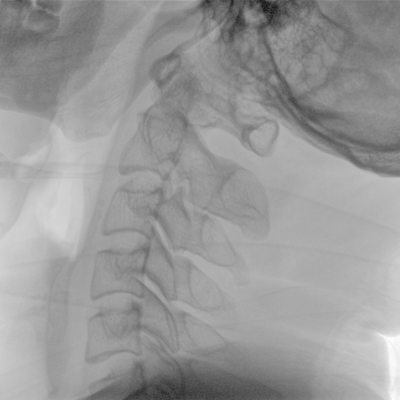

骨科: 经皮锥体成形术、经皮椎间盘臭氧治疗术、胸脊椎固定、骨活检、腰椎内固定术等。

优质平板探测器、可灵活升降调节SID、独特图像处理系统、高品质滤线栅,大视野成像清晰不失真。